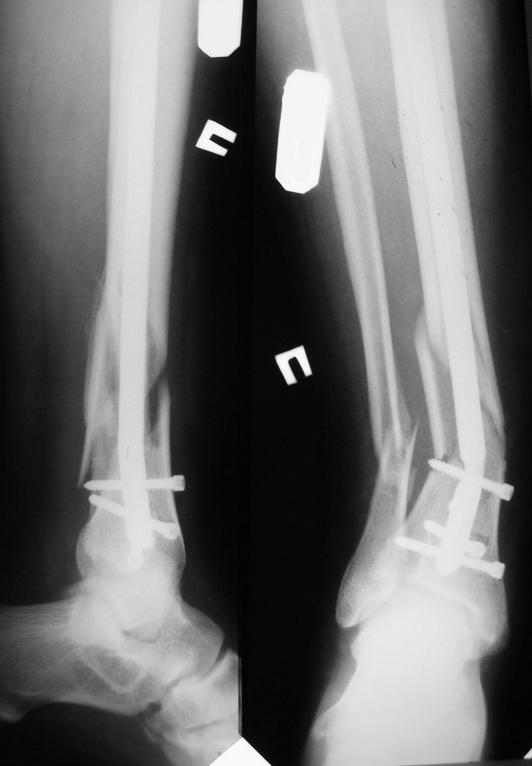

Уважаемые коллеги! Помогите советом! Через 6 дней после операции больной упал, загнул

титановый тибиальный блокирующий стержень диаметром 10 мм.

Больной 36 лет, Ds: оскоьчатый перелом костей правой голени в н/3 со смещением. 3.02.09.

выполнен интрамедулярный блокирующий остеосинтез б/берцовой кости титановым стержнем

диамерт 10 мм. 9.02.09. больбной упал в палате, загнул стержень.